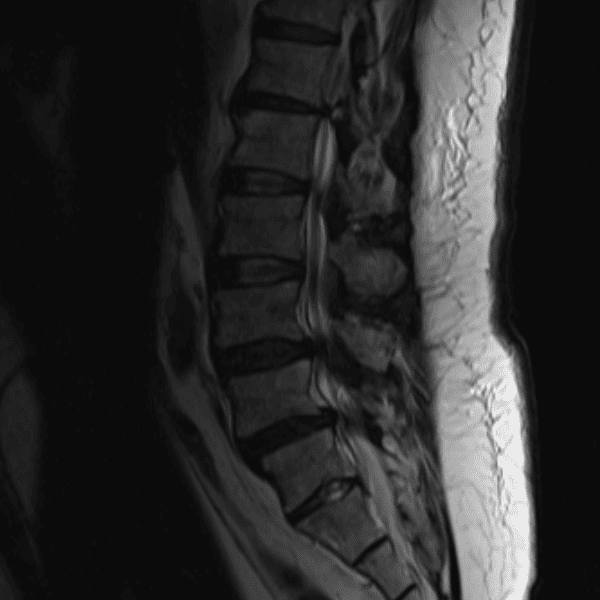

Simulates call by including subtle or difficult cases and some normals.

35 cases